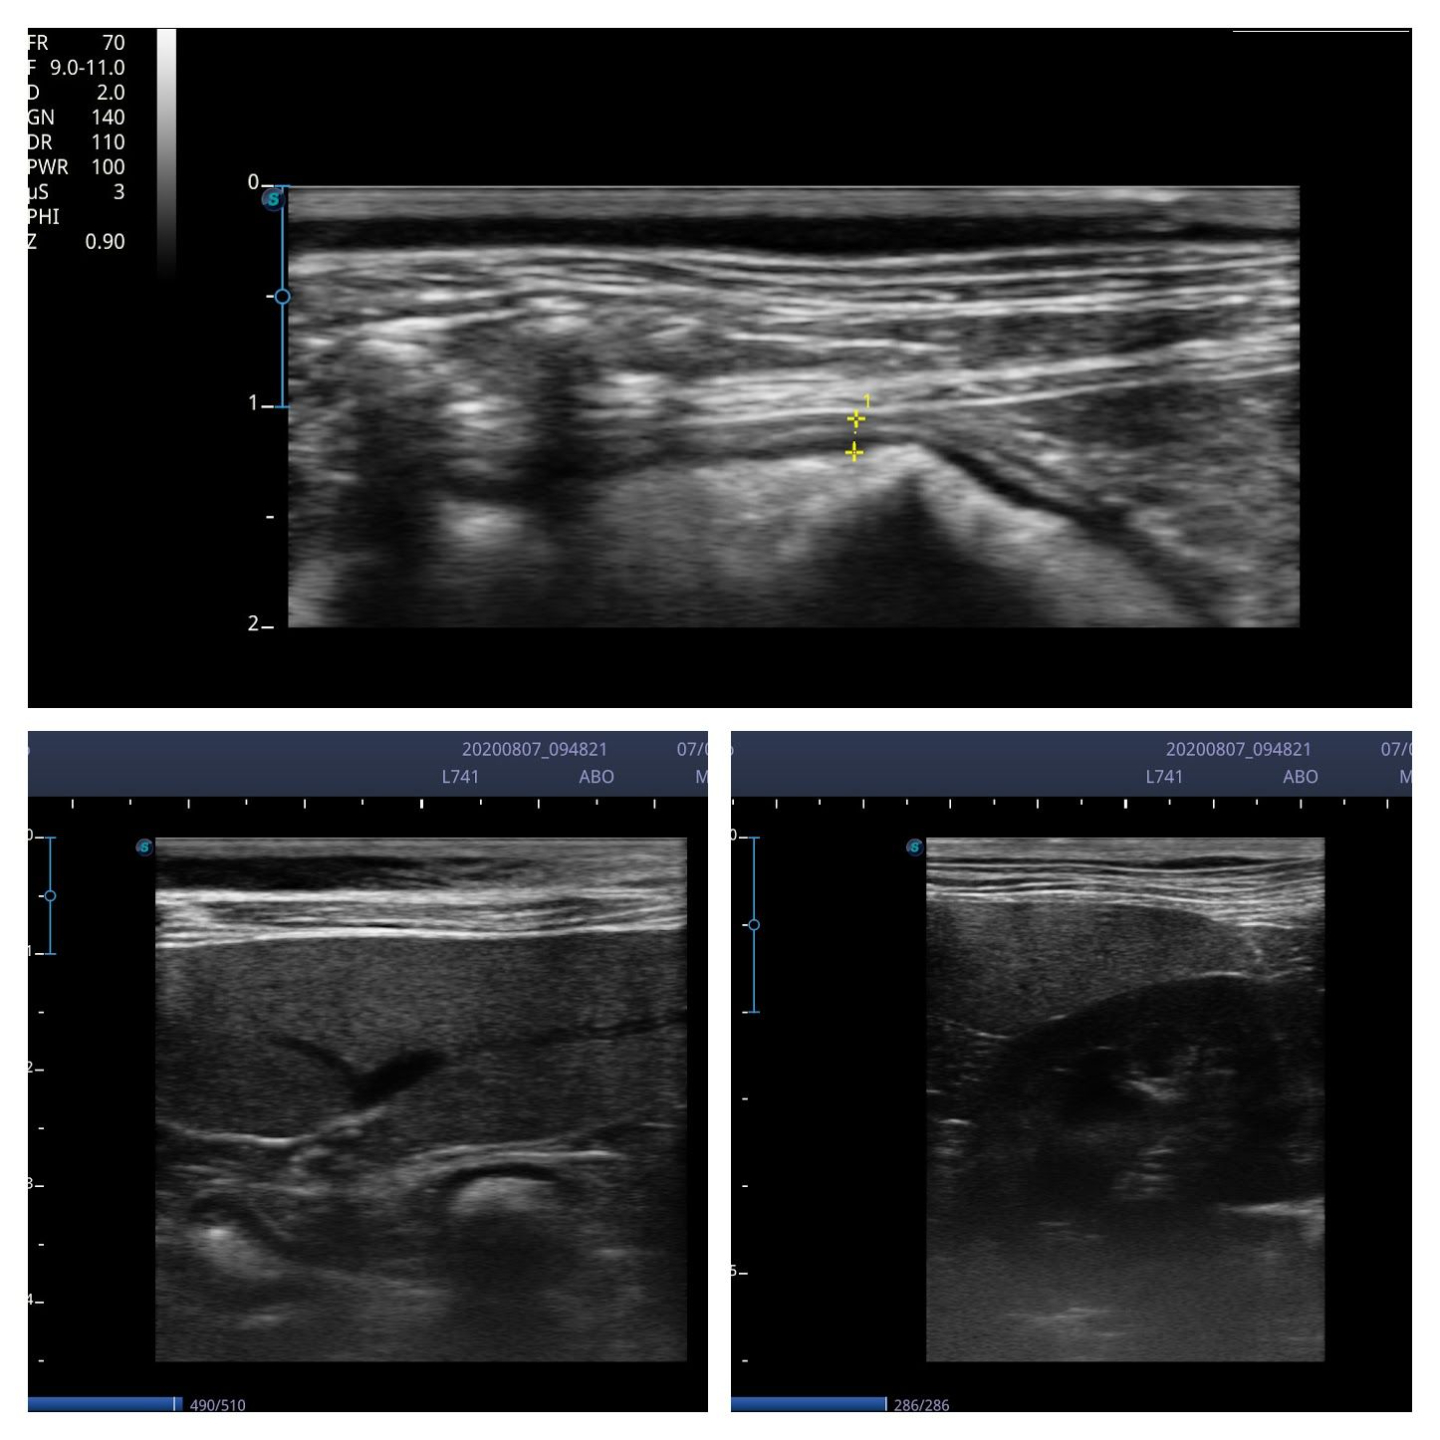

I scanned with the microconvex C613 probe (4-13MHz) and the linear L741 (4-16MHz). Although the linear probe gives great images, the 4.5cm footprint does make maneuverability around a small cat abdomen a little tricky. The microconvex probe was used in a few dogs up to 20Kg and managed to view the liver perfectly well.